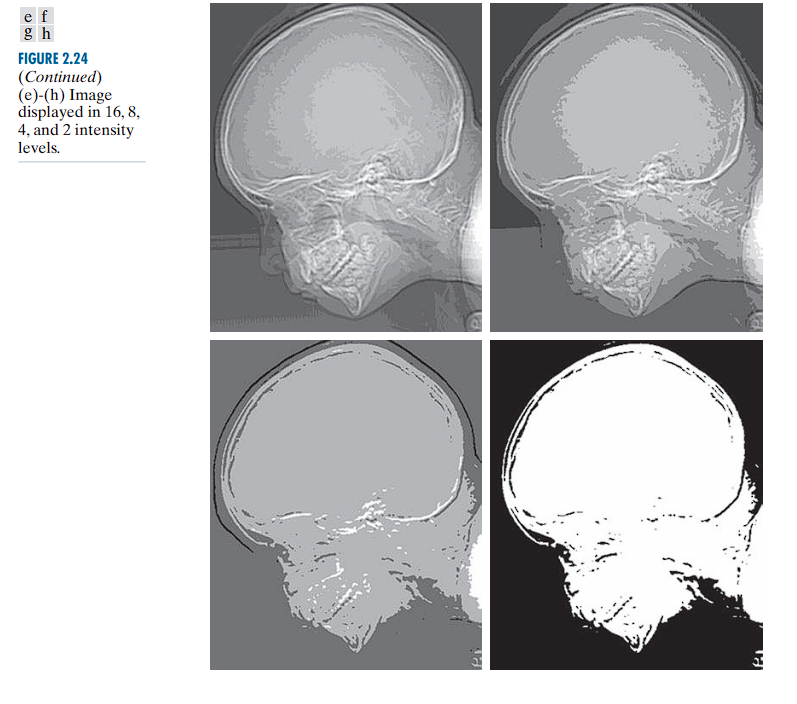

Intensity Resolution

Intensity resolution refers to the number of distinct gray levels (or intensity levels) that can be represented in an image.

Bit depth defines the number of bits used to represent the intensity value of each pixel in a digital image. It determines the total number of available tonal (gray) levels that can be encoded.

A b-bit image has 2^b grey levels.

- 8-bit → 256 levels (0–255)

When too few intensity levels are used for an image that contains smooth gradients (such as a clear sky or a curved surface), an artifact known as posterization or false contouring can appear.

There is a progressive degradation in quality as the number of intensity levels reduces from 256 to 2.

Low resolution (2–16 levels) often reveals unintended contours and artifacts.